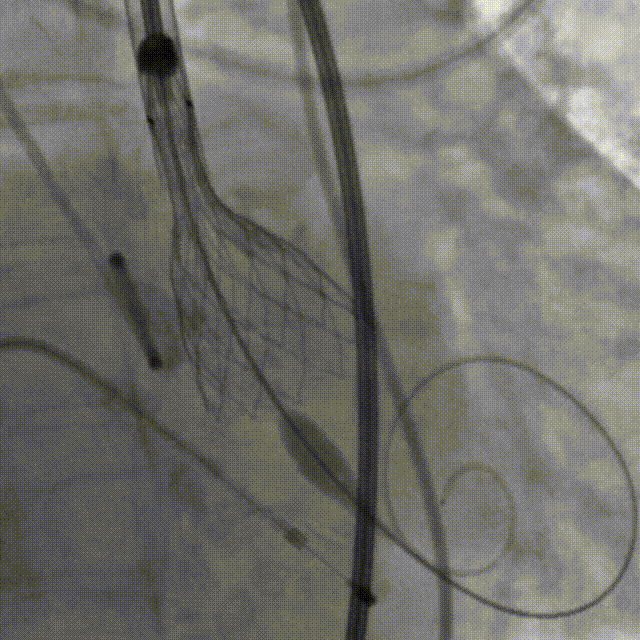

血管比较迂曲,无法确认导丝一定能够通过侧枝循环,故计划是:更换为左

mm球囊),并优先准备av23的瓣膜装载(备av26瓣膜);由于股动脉入路情况

22mm球囊扩张冠脉造影手术过程主动脉根部解剖广东省人民医院李捷教授

瓣膜完成定位pci后左冠明显改善左冠血管纤细升主动脉内径增宽穿刺